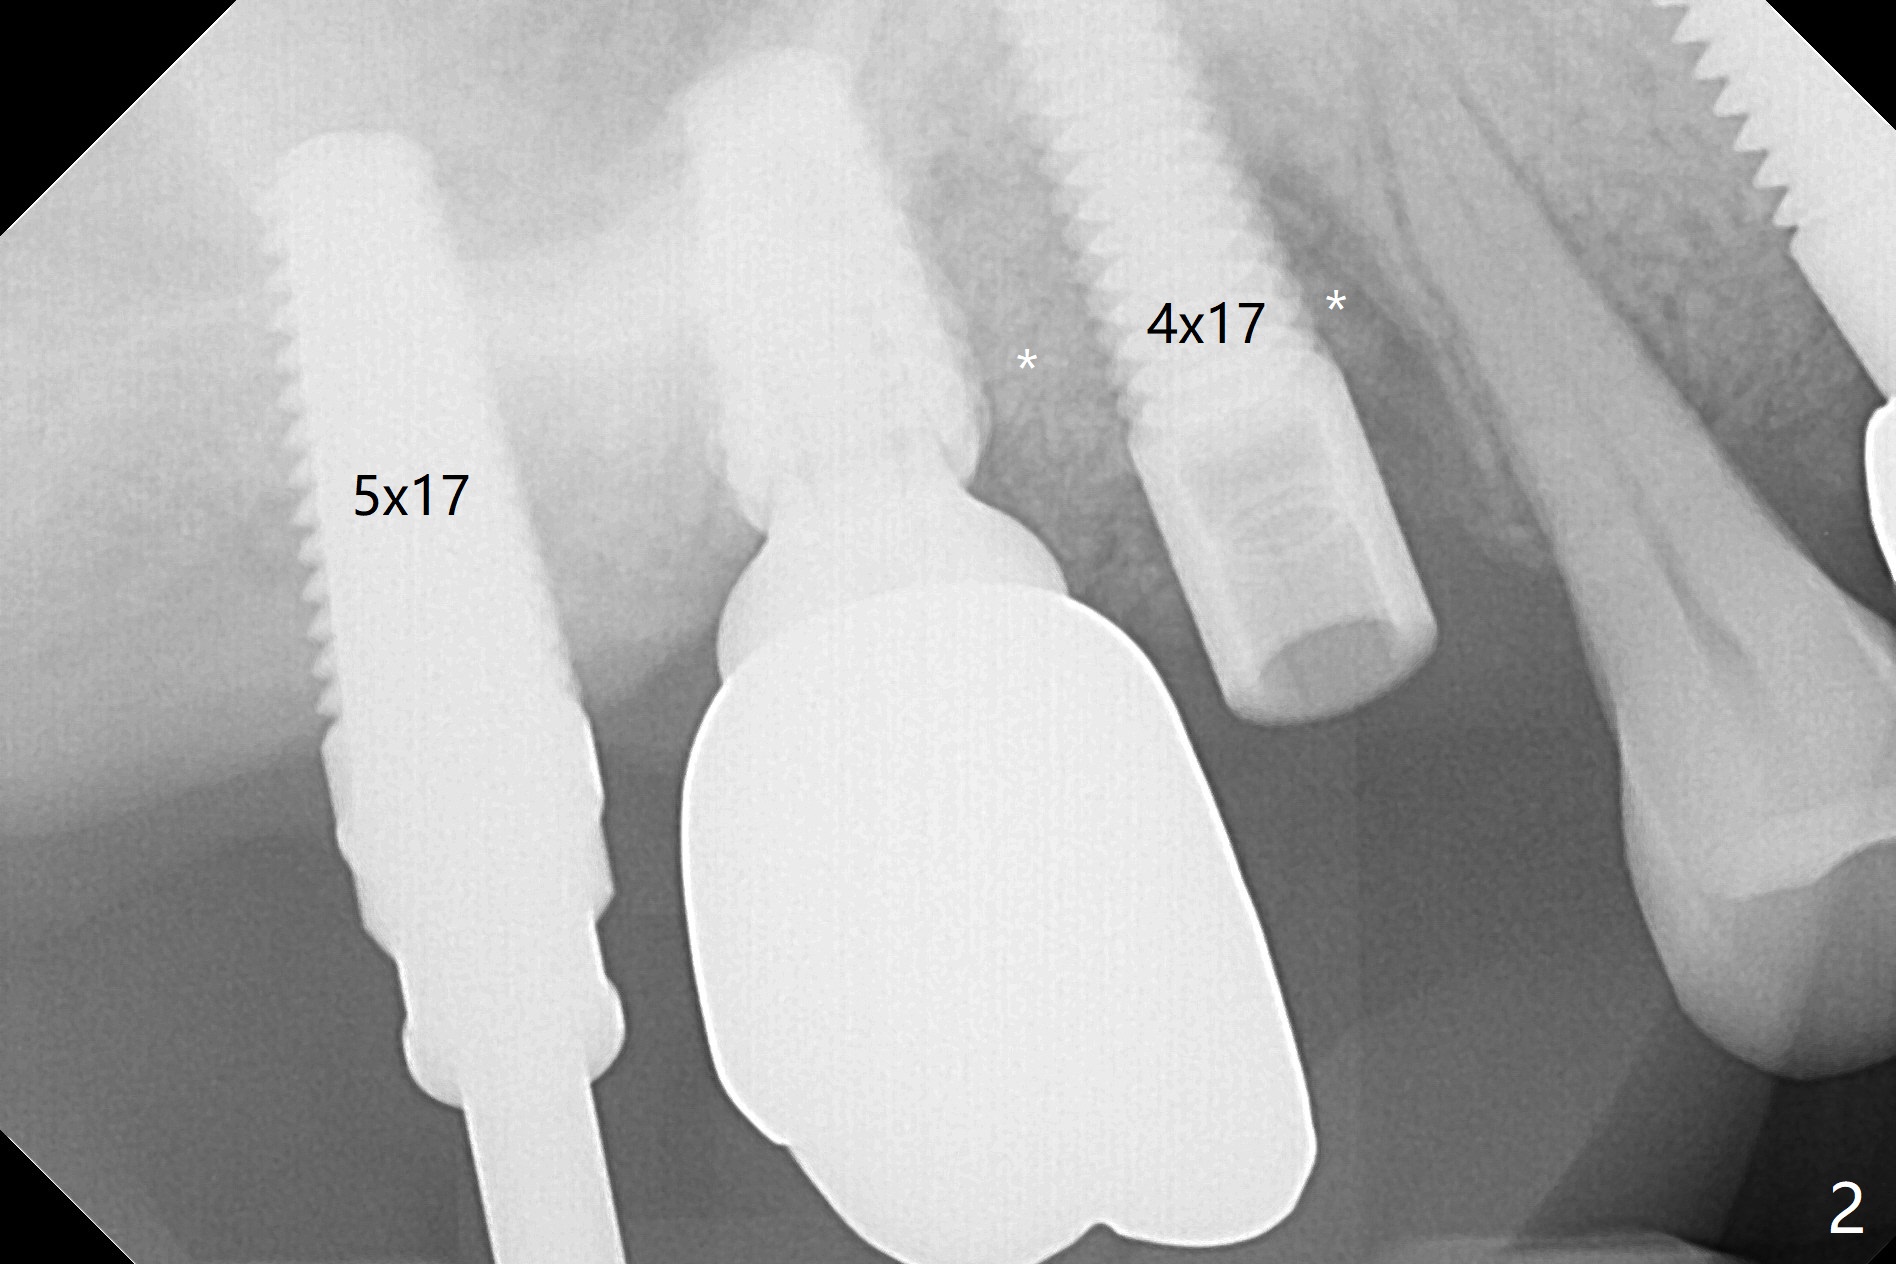

After osteotomy using bone-level implant guide at #4, the crown and abutment at #3 has to be removed to place a 4x14 mm tissue-level dummy implant because of the narrow space of #4 and implant placement angulation (Fig.1). Following initial placement of a final 4x17 mm implant and bone graft (Fig.2 *), the crown and abutment of #3 and the guide are reseated for correct implant trajectory. The guide has to be removed for final depth control. With the same mode, a 5x17 mm tissue-level tap is used at #2 following bone-level osteotomy with guide. A 5x14 mm tissue-level implant is placed with >50 Ncm (later placed deeper), while more bone graft is inserted mesial of #4 implant with a 3.5x5 mm abutment (Fig.3 *). Bone graft is introduced into the sinus using guided sinus lift kit (Fig.4,5 (CT sagittal and coronal sections)) * (D: distal, P: palatal)). The coronal half of the implant at #4 is covered by bone graft (Fig.6 *) buccal (B) and palatal within the deep socket. The implants at #2 and 4 seem to have osteointegrated nearly 5.5 months postop (Fig.7,8 (BW)). A 4.5x5 mm unipost is later placed at #2 with long chamfer margin. It appears that the abutment at #3 is wide. The hex is worn. It changes to a 5.5x7(4) mm one. After abutment adjustment for parallelism, a provisional FPD is fabricated. The latter will be adjusted for papilla formation between implants to reduce food impaction.